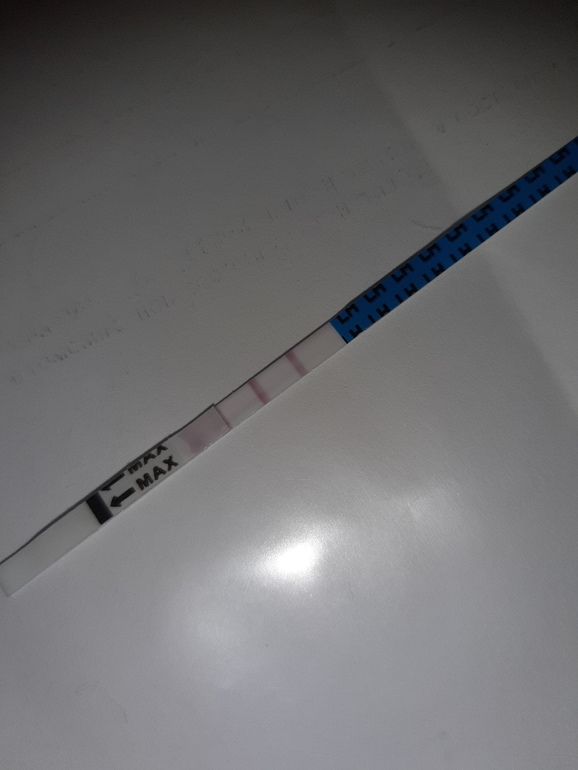

Я даже тест у меня они есть приеду замочу ,что бы узнать их достоверность .кароче я улыбнулась

))))  ТЕСТ В КОМЕНТАХ

ТЕСТ В КОМЕНТАХ

ДЕВЧЕНКИ, ТЕСТ НА ОВУЛЯЦИЮ * Я РОДИЛСЯ* НЕ ВРЕТ!!! ПРОВЕРЕННО

ТЕСТ НА ОВУЛЯЦ

ТЕСТ НА ОВУЛЯЦ  ИЮ я родился фирма.

ИЮ я родился фирма.